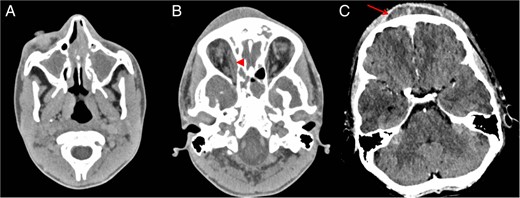

An initial computed tomography (CT) head with contrast (Fig. 1) revealed completely occluded sphenoid, ethmoid, frontal and maxillary sinuses. There was a rim enhancing area of low attenuation over the frontal bone in keeping with a subperiosteal collection, although no bony erosions were apparent. No intracranial spread was seen, although there was a small subperiosteal collection in the right orbit medial to the right medial rectus muscle.

Post-contrast axial CT (A) shows opacified paranasal sinuses keeping with sinusitis. Right orbital subperiosteal abscess (arrowhead) and scalp subperiosteal abscess (arrow) consistent with Pott's puffy tumour seen on CT (B and C).